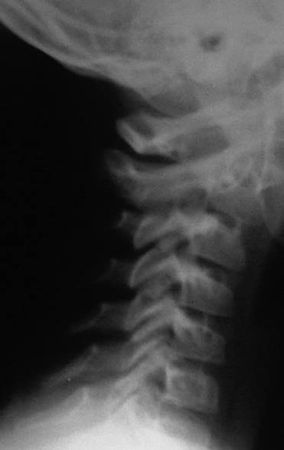

Отсутствие лордоза у детей до 16 лет (рис. 4.8)

Отсутствие лордоза или легкое кифозирование в среднешейном отделе позвоночника обнаруживается на сагиттальных рентгенограммах в среднем положении головы у 14 % здоровых детей с 8 до 16 лет [7]. Делая заключение необходимо учитывать особенности укладки (рис 4.8 В)!

Рис. 4.8. Отсутствие лордоза у детей до 16 лет А – нормальный лордоз у подростка 14 лет.

Б – боковая рентгенограмма здорового ребенка 9 лет. Прямой сагиттальный профиль. Вариант нормы.

В – пологое кифозирование на уровне CII–CV у ребенка 6 лет. Снимок сделан лежа – видна поверхность стола, и голова наклонена вперед. Сагиттальный профиль связан с особенностью укладки